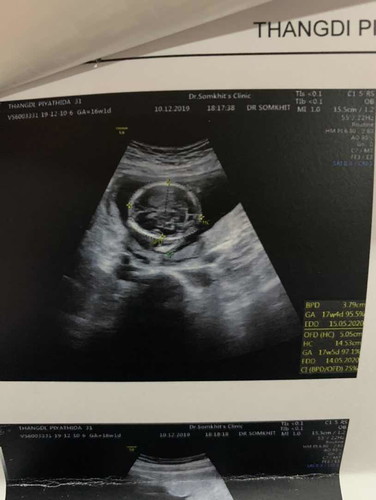

อายุครรภ์ 16สัปดาห์ไปซาวน์มาหมอบอกน้องมีน้ำในสมอง แต่หมอยังไม่ส่งต่อค่ะรอซาวน์ดูเดือนหน้าเพราะน้องยังเล็กอยู่ค่ะ แม่ๆเคยเจอเหตุการณ์แบบนี้กันไหมคะแล้วผลเป็นยังไงบ้างรบกวนเล่าสู่กันฟันหน่อยคะ แม่บ้านนี้ไม่สบายใจเลยคะ(น้องมีตัวที่ใหญ่เร็วกว่าอายุครรภ์จริงเกินไป8วันค่ะอันนี้หมอบอกว่าดีค่ะแต่อยากฟังแม่ๆบ้านอื่นที่มีประสบการณ์ค่ะ) ขอบคุณนะคะ